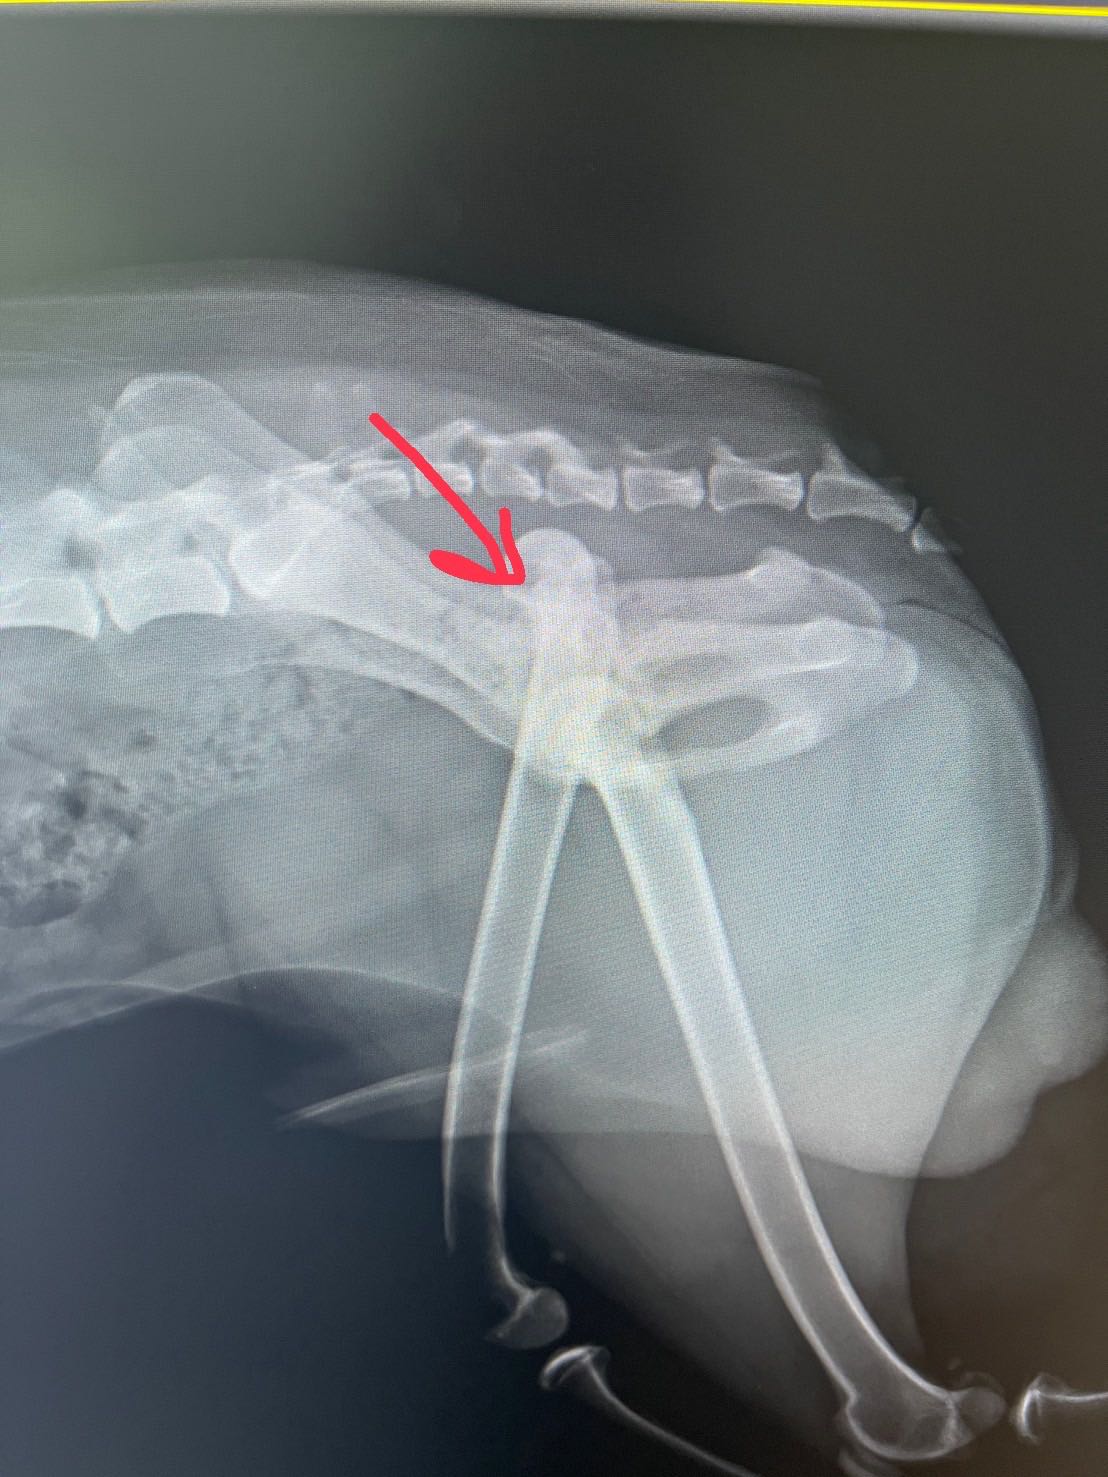

วันศุกร์ที่ 28 ที่ผ่านมาน้องหมาเรากระโดดขึ้นเตียงเพราะวิ่งเล่น แต่ก้าวไม่พ้นขอบเตียง ร่วงจากเตียงจนช่วงสะโพกกระแทกพื้น สะโพกหลุด แต่ไม่มีกระดูกร้าวหรือแตกนะคะ

ในวันแรก รีบพาไป รพ.สัตว์ใกล้บ้าน หมอตรวจเบื้องต้น ได้ฟิล์ม x-ray มา